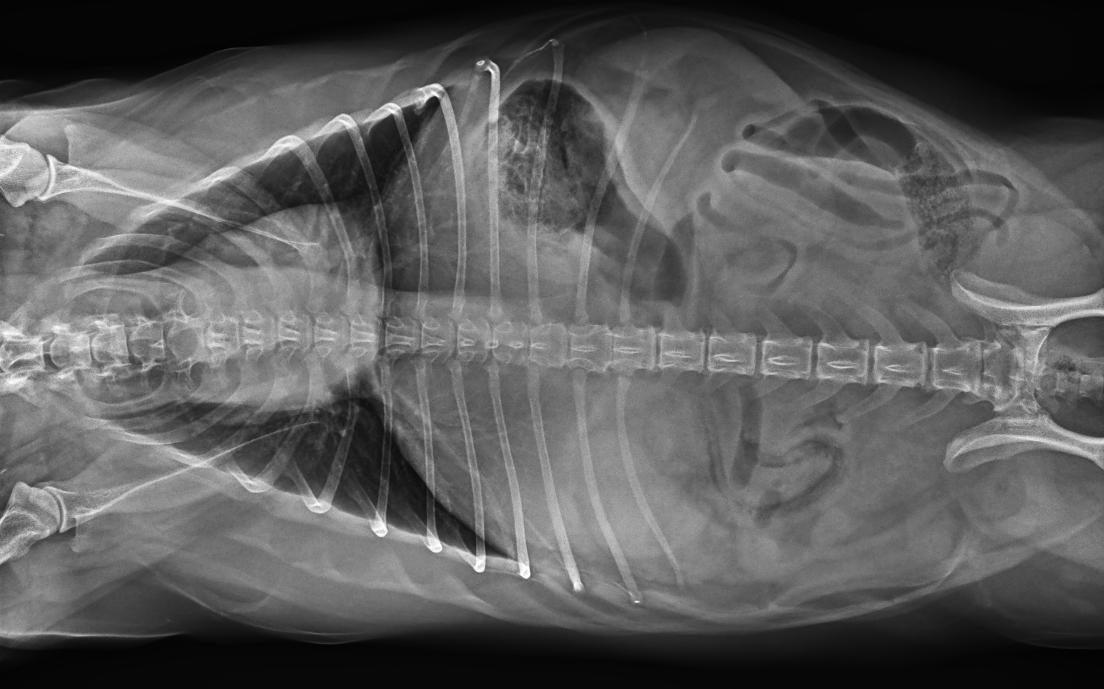

專為拍攝寵物設(shè)計(jì) VET1900 寵物DR

● 17*17大尺寸平板探測(cè)器,獲得高質(zhì)量圖像

● 優(yōu)異的空間分辨率及信噪比,提升圖像質(zhì)量

● 采用線噪聲消除技術(shù),使成像質(zhì)量提升40%

● 智能高效的圖像處理軟件,大幅提升圖像質(zhì)量